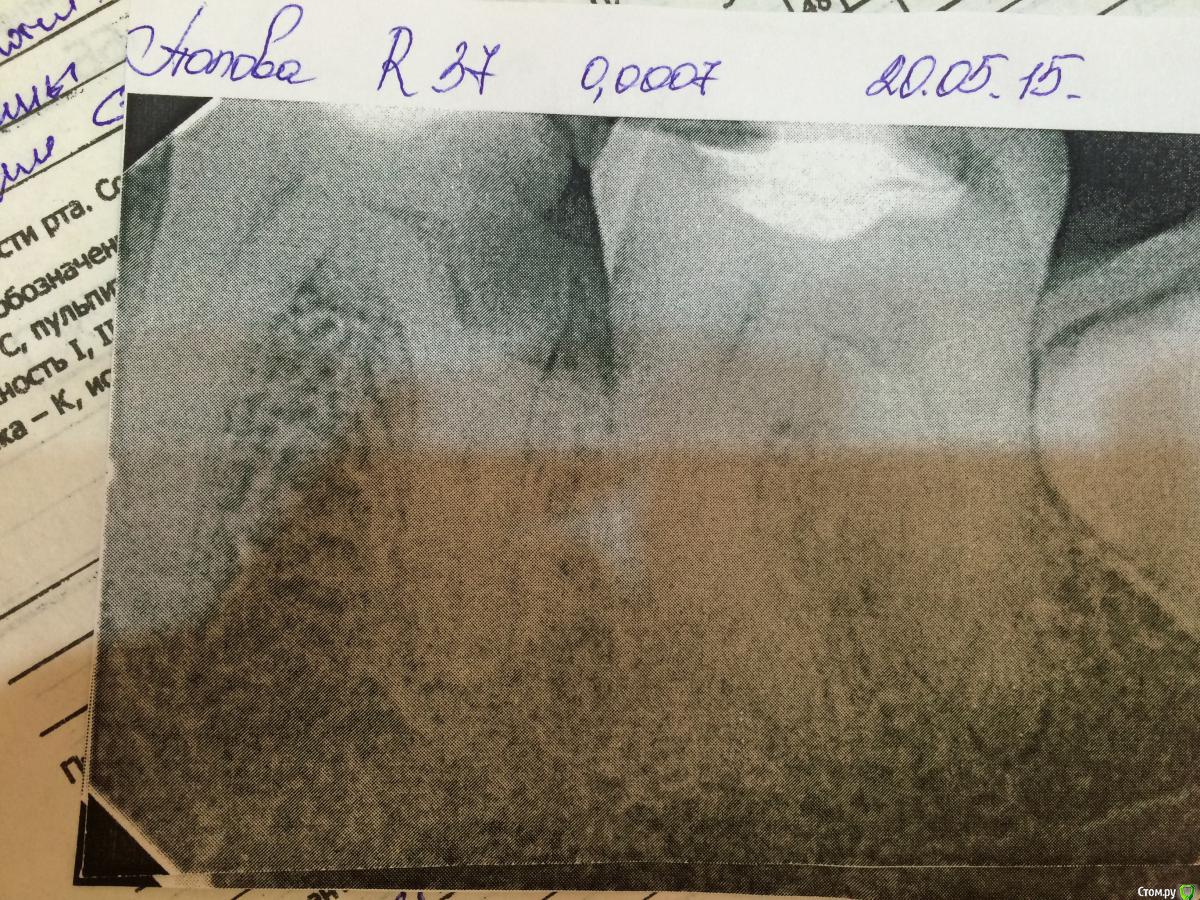

Belladonna.feo Опубликовано 28 мая, 2015 Поделиться Опубликовано 28 мая, 2015 (изменено) 36 зуб. Диагноз: хр.пульпит. Медиальные каналы пройдены до апекса(исходя из данных Р-снимка и апекс локатора), дистальный на 2/3 и далее нет прохода. Апекс локатор показывает выход за апекс, на снимке будто в канале. Пациент под анестезией, поэтому боли нет. Кровотечения из канала тоже. Что посоветуете делать? An. Morbi: пациентка пришла с жалобами на ноющие боли в левой челюсти. Указывала на 37 зуб. После просмотра снимка пришли к решению, что причина болей пульпит в 36 з, по причине глубокой кариозный полости. На 37 разрежение в обл дист корня и кариоз полость под пломбой. Ретинированный 38. В 36 на устьях был оставлен нон арсеник на 8 дней. Далее вновь анестезия и депульпация. Медиальные обработаны протепейрами 06 до 20 номера. Дистальный не пускает и не кровоточит. Показывает апекс. Изменено 28 мая, 2015 пользователем Belladonna.feo Ссылка на комментарий

Ker Опубликовано 10 марта, 2016 Поделиться Опубликовано 10 марта, 2016 (изменено) кстати вглядитесь во второй снимок, там видно докуда канал идет. Нет никакого перфо там. А инструмент не идет из опилок. Имхо. Изменено 10 марта, 2016 пользователем Ker Ссылка на комментарий